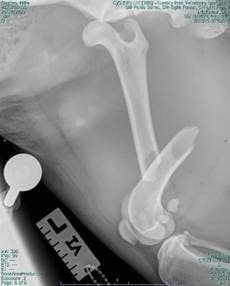

Once Millie had been successfully treated by the soft tissue surgery team, it was time for Lumbry Park’s orthopaedic surgery Specialists to step in and perform a fracture repair to her femur and to stabilise her hip. The femoral fracture was stabilised using steel plates and screws, to ensure a strong and durable repair. Simultaneously, her hip dislocation was corrected and secured using a ‘hip toggle’ to restore the joint’s stability.

Lateral Xray of Millie’s femur fracture and hip dislocation